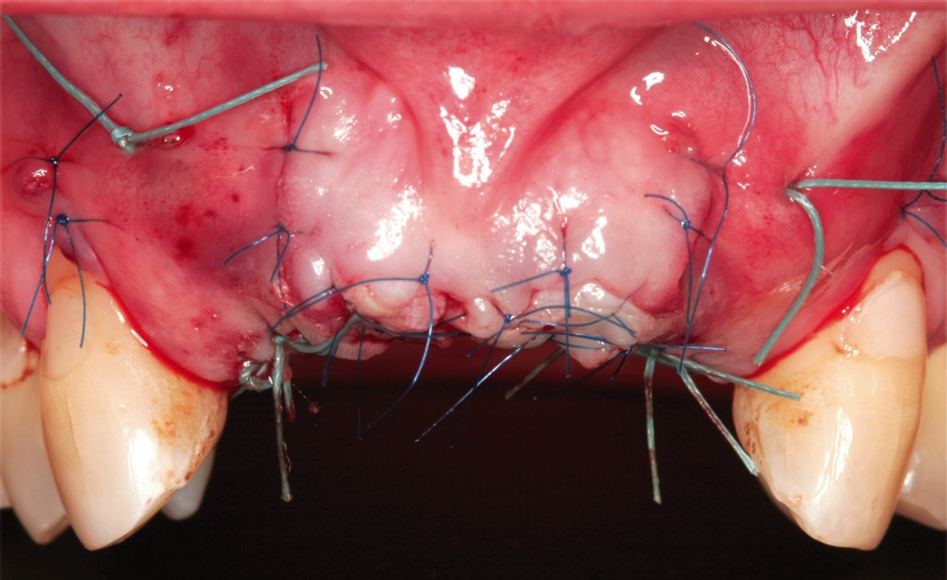

Anschließend wurde das Implantatbett durch den Ring vorbereitet und ein Straumann Bone Level Tapered (BLT) Implantat ø 3,3 mm gesetzt (Abb. 7 und 8). Insgesamt erfolgte die Implantation von zwei maxgraft® bonerings 6 mm und zwei Straumann BLT Implantat ø 3,3 mm 10 mm (Abb. 9). Zur Unterstützung der Weichgewebeheilung wurde platelet-rich fibrin (PRF) aus dem Blut der Patientin gewonnen (Abb. 10). Das PRF wurde sowohl in Verbindung mit dem Knochenersatzmaterial (cerabone®) (Abb. 11), als auch als Membran über der Barrieremembran (Jason® membrane) (Abb. 12) eingesetzt. Zum Erhalt der 1er Schneidezähne wurde eine Socket Preservation mit einem Knochen-Schleimhaut-Transplantat aus der tuber maxillae durchgeführt (Abb. 14 und 15). Explantation erfolgte mithilfe eines 6er Trepans rechts und links aus dem Kieferkamm (Abb. 14).

Die Knochenringtechnik mit allogenem Knochenersatzmaterial (maxgraft® bonering) ist eine geeignete Variante zur Augmentation von dreidimensionalen Defekten. Ebenso stellt sie eine geeignete Alternative zur Entnahme von autologem Knochen und Blockaugmentationen dar. Dabei wird dem Patienten die Entnahmestellenmorbidität erspart und darüber hinaus die Behandlungszeit verkürzt. Gleichzeitig ist die Patientenakzeptanz hoch wegen der schnelleren Versorgung des Patienten mit finaler Prothetik. Entscheidende Faktoren für den Erfolg der Augmentation stellen ausreichende Weichgewebemobilisation sowie spannungsfreie und speicheldichte Nähte dar [6] (Abb. 13, 17 und 18).